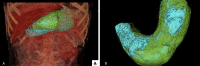

Figure 2

Figure 2. (A) 3D rendered image of surrounding organs and intestine showing stomach bezoar (blue) in the stomach (green) (B) isolated 3D rendered image of stomach bezoar (blue) within the stomach wall (green)